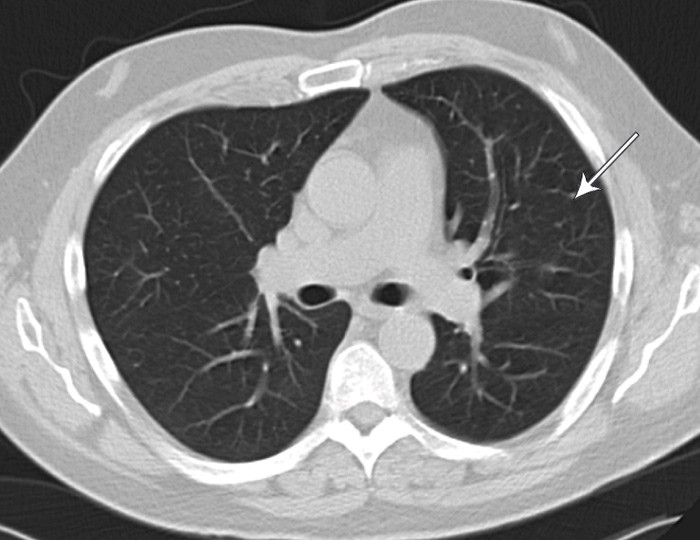

Pasienten gjennomgikk en omfattende utredning. Man fikk avkreftet differensialdiagnostiske muligheter som er nevnt i litteraturen (fig 3), med unntak av Wegeners granulomatose som ikke sikkert kunne utelukkes. Den videre utredningen ble derfor rettet mot dette. Det eneste positive funnet var c-ANCA, som var svakt positiv initialt, men senere innenfor referanseområdet. Blodprøver for øvrig var normale. Det ble ikke funnet hudforandringer, hjerte- eller nyreaffeksjon. CT av tinningbein viste væske og bløtdelsfortykkelse i mellomøret og fortettede mastoidalceller på venstre side. Ved CT av bihuler så man hypoplastisk venstre maksillærsinus med slimhinnefortykkelse og væskespeil, men ingen granulomer. Biopsi av respiratorisk slimhinne konkluderte med uspesifikk kronisk betennelse, og ingen vaskulitt eller granulomer. CT thorax viste mulig progresjon av én av de små uspesifikke nodulære fortetningene som ble påvist i venstre overlapp ved sykdomsdebut, men forandringen var ikke tilgjengelig for biopsi (fig 4).